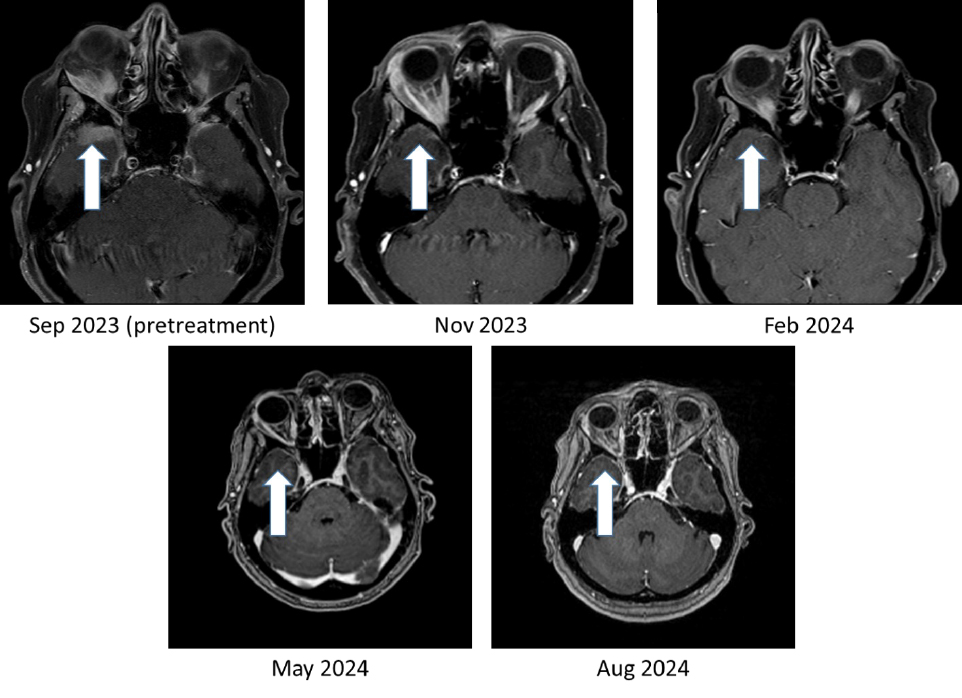

Figure 1: Bria-IMT™ regimen resulted in 100% resolution of tumor in the right temporal lobe region of the brain

As shown in Figure 1, the right temporal lobe lesion is no longer detectable on the images taken at 8 months and 11 months on the Bria-IMT™ combination regimen. The orbital lesion has continued to shrink markedly (Figure 2). In addition, her tumor markers (blood tests that correlate with the amount of tumor in the body) remain markedly decreased from her pre-treatment levels.